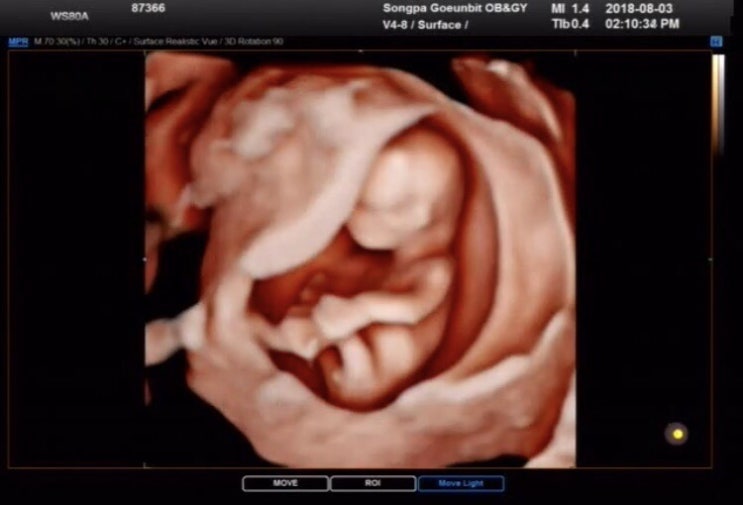

임신15주 성별확인 초음파/ 임신15주 첫태동,배뭉침/임신성 갑상선기능항진증,임산부 저혈압/2차 기형아검사

시험관 임신으로 서울역차병원을 졸업하고 송파 고은빛산부인과로 전원했다 송파 고은빛산부인과로 전원한 ...